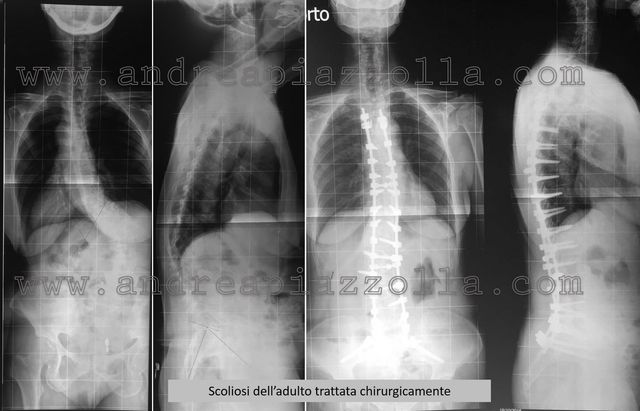

Trattamento Della Scoliosi Bari Dottor Andrea Piazzolla